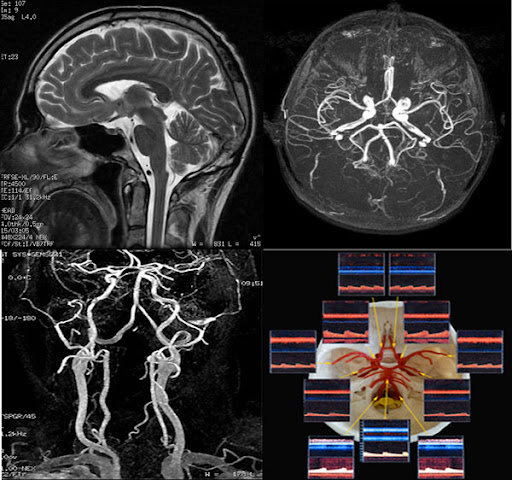

MRI는 인체 내의 수소 원자의 자기적 성질을 이용하여 이미지를 생성합니다. 강력한 자기장이 수소 원자를 정렬시킨 후, 라디오 파를 통해 이들을 자극하여 방출되는 신호를 수집합니다. 수집된 신호는 컴퓨터에 의해 해석되어 이미지를 만들어 내는데, 이 과정에서 세부적인 이미지가 생성되어 체내 구조를 명확하게 볼 수 있게 됩니다.

MRA는 MRI의 기법을 기반으로 하므로, 기본적으로는 동일한 작동 원리를 가지고 있지만, 약간의 차이점이 있습니다. MRA는 특히 혈관을 시각화하는 데 최적화되어 있으며, 주로 조영제를 사용하여 혈관을 더욱 뚜렷하게 구분합니다. 조영제는 혈관 내에서 신호의 차이를 만들어 신호 강도를 높여줍니다. 이로 인해 혈관의 형태와 상태를 더욱 명확하게 시각화할 수 있습니다.